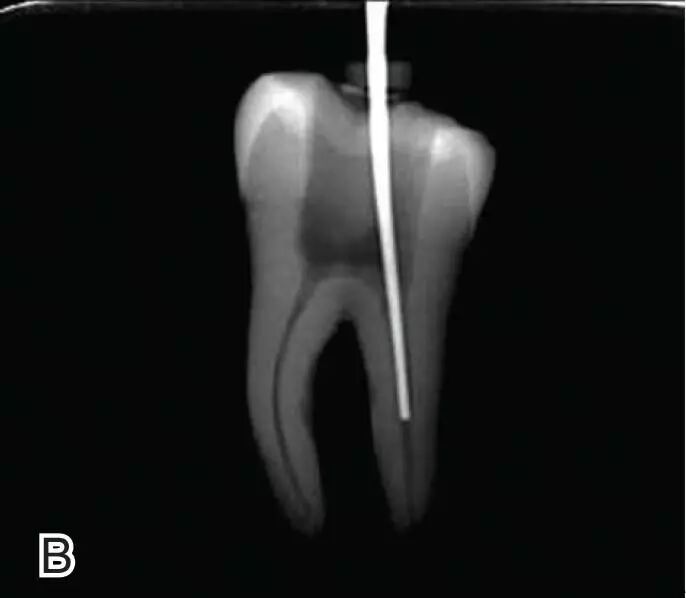

试尖

选择非标准牙胶尖(如0.04、0.06 锥度牙胶尖)作为主尖,型号一般与根管预备最大号的器械型号一致,能到达距根尖0.5~1 mm 处,主尖尖段与根管壁紧密接触。拍试尖X 线片进行确认。